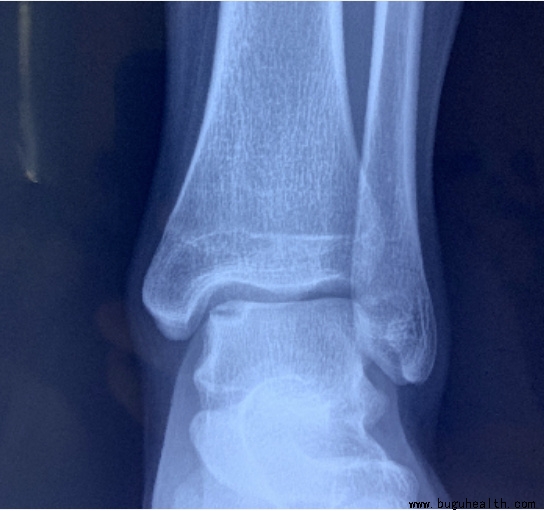

从X光片上,我们只能看到踝关节的骨性的结构,这也是为什么有时候医生会要求再做核磁共振的检查来看看踝关节的周围,韧带、肌肉以及肌腱的情况。

在一些长期踝关节不稳定的患者中,距骨软骨表面常常会出现下面的软骨磨损,引起踝关节的疼痛。